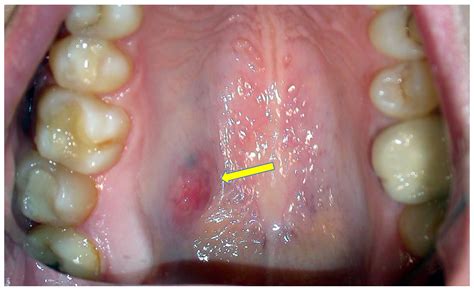

• White patches or sores on the soft palate

• Persistent sores or ulcers

• Lumps or masses in the mouth